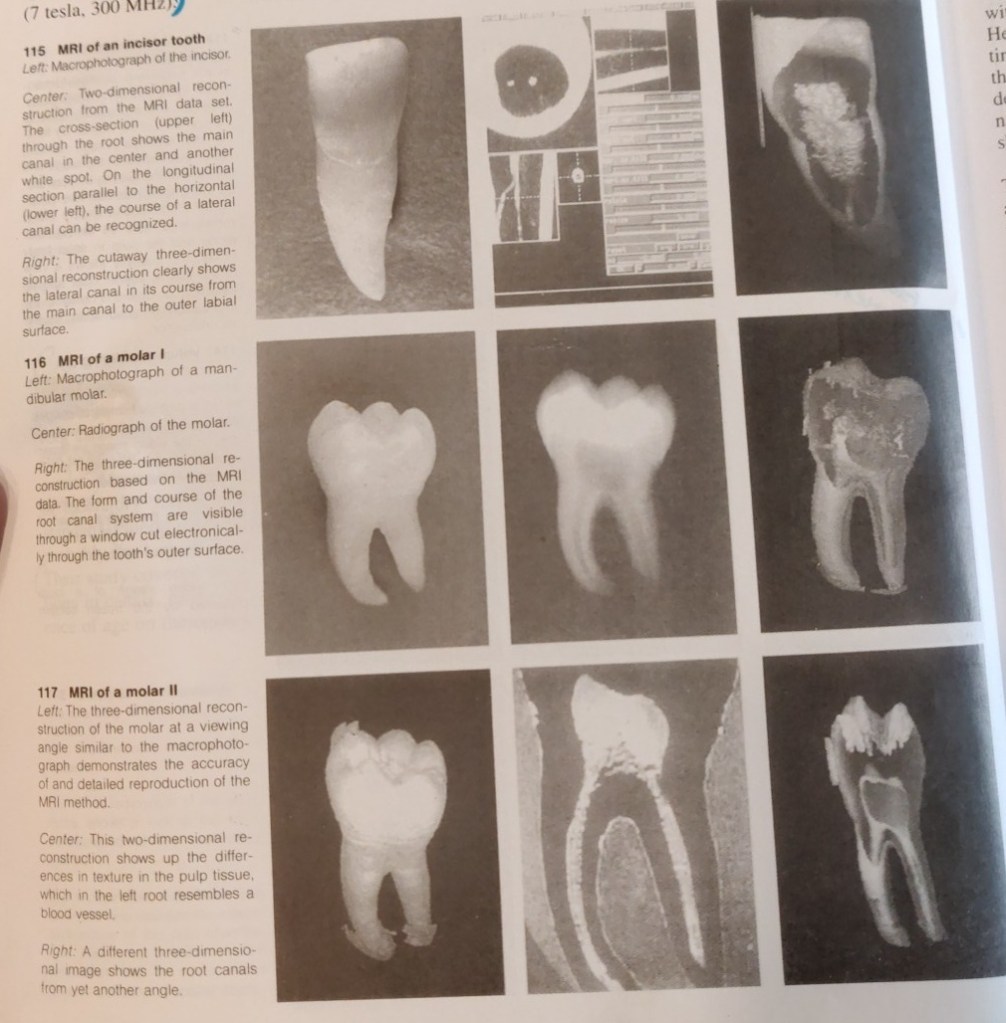

Normally, only vague images of bone and tooth can be obtained by magnetic resonance tomography (MRT). Baumann (1995; Baumann et al. 1993 a-d) was the first to succeed in producing a visual representation of the H+ protons of dental hard structures by using measurement sequences from solid body spectroscopy and especially strong magnetic fields. The soft pulpal tissue is elusive becuase of the small scale of the MRI. The first magnetic resonance images have now been realized with BRUKER SPECTOMETER AMX 300 WB (7 tesla, 300MHz).

Computer processing of data from the MRI permits creation of two and three-dimensional reconstructions that can be rotated and sectioned (Bauman 1995; Baumann and Doll, in press). Now for the first time we have a nondestructive method that does not use ionizing radiation. Two-dimensional sections of molars give rise to the hope that it will be possible to depict differences in tissue texture, which would be a great aid in the diagnosis of pulpitis. The spatial reconstruction of an individual canal configuration would be a great enlightment for endodontic treatment.